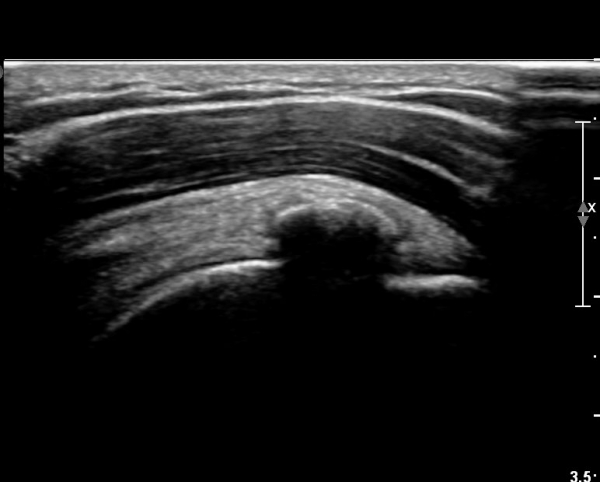

±Ø»ó°Ç Ⱦ´Ü¸é°Ë»ç¿¡¼­µµ ±Ø»ê°Ç³» ¼®È¸È­ µ¢¾î¸®°¡ °üÂûµÈ´Ù(»çÁø 2).

±Ø»ó°Ç Á¾´Ü¸é °Ë»ç»ó¿¡¼­ Á¡¾×³¶³»¿¡ ÁÖ»ç¹Ù´ÃÀÌ À§Ä¡ÇÑ °ÍÀÌ º¸ÀδÙ(»çÁø 3).

Á¡¾×³¶³» ÁÖ»ç ÈÄ ÁÖ»ç¹Ù´ÃÀ» ¹Ýº¹ÀûÀ¸·Î ´õ ÁøÀÔ½ÃÄÑ ¼®È¸¸¦ ºÐ¼âÇÑ´Ù(»çÁø 4).